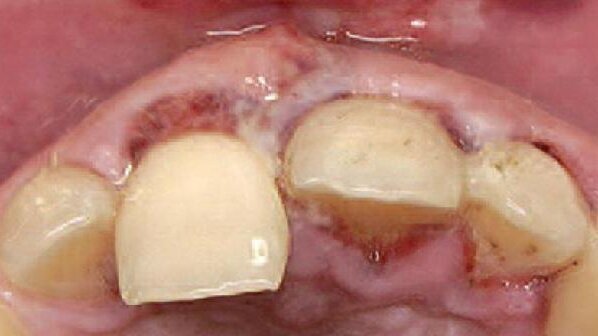

Pacjent zgłosił się w dniu urazu. W jego wyniku złamany został korzeń siekacza przyśrodkowego prawego (Ryc. 1-3). Z powodu dużego lęku przed zabiegami z zakresu chirurgii jamy ustnej, pacjent odstąpił od proponowanej ekstrakcji złamanego zęba z jednoczesnym zabiegiem augmentacji i regeneracji kości przed przyszłą implantacją. W związku z tym jedynie usunięto ząb wraz ze złamanym korzeniem i zabezpieczono ujście zębodołu za pomocą mostu adhezyjnego z przęsłem wykonanym z korony utraconego zęba. (Ryc. 4-5).

Po upływie ok. 7 miesięcy pacjent ponownie pojawił się w klinice celem kontroli, zgłaszał też dyskretne dolegliwości ze strony siekaczy górnych po stornie lewej (Ryc. 6). Wyraził gotowość do zabiegu implantacji, jednakże całkowicie odmówił wykonywania dodatkowych procedur, takich jak augmentacja lub regeneracja kości oraz przeszczep tkanki łącznej z podniebienia celem augmentacji od strony przedsionka. Lęk pacjenta budził konieczność wytworzenia rany-dawcy tkanki przeszczepianej. Nadmienić warto, iż zęby sieczne w szczęce lewej wyleczono endodontycznie i wspomniane dolegliwości ustąpiły.

Z powodu widocznego ubytku w wymiarze wargowo-podniebiennym od strony przedsionka w projekcji brakującego zęba siecznego prawego przyśrodkowego (Ryc. 6-8) pacjent wyraził zgodę jedynie na augmentację z użyciem błon kolagenowych.